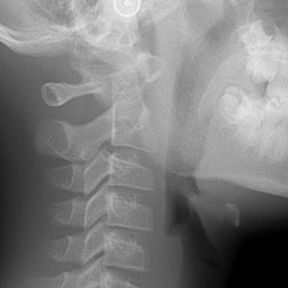

얼굴 골격의 성장에 문제가 있는지를 파악하기 위한 적절한 시기는 초등학교 입학 전인 6-7세경입니다. 이때는 유치에서 영구치로 교환되는 시기로서 부정교합 여부가 결정되는 중요한 시기이므로 이 시기를 잘 관찰하여 부정교합을 예방하는 것 또한 중요합니다. 교정의 정확한 시기는 6개월 간격으로 치과에 정기적으로 내원하여 성장 분석을 받은 후 결정하는 것이 좋습니다.